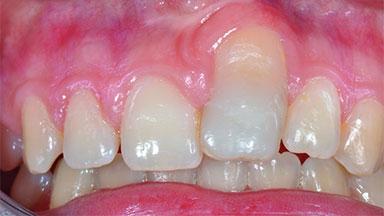

Replacement of an Ankylosed Central Incisor with a Gingival Recession: Tooth Extraction with Socket Grafting and Late Implant Placement with Simultaneous Contour Augmentation

In 2008, a healthy 15-year-old female, non-smoking patient presented at our clinic with a major esthetic problem of tooth 21. Her dental history revealed that the tooth had been avulsed by trauma years before. As a result, the replanted and temporarily splinted tooth had ankylosed and was in severe apical malposition. The ankylosed tooth exhibited a significant gingival recession that disturbed the patient greatly. Due to the patient’s low age and with her skeletal growth not completed, periodic follow-up visits were scheduled to monitor the situation until the patient was old enough for implant therapy.